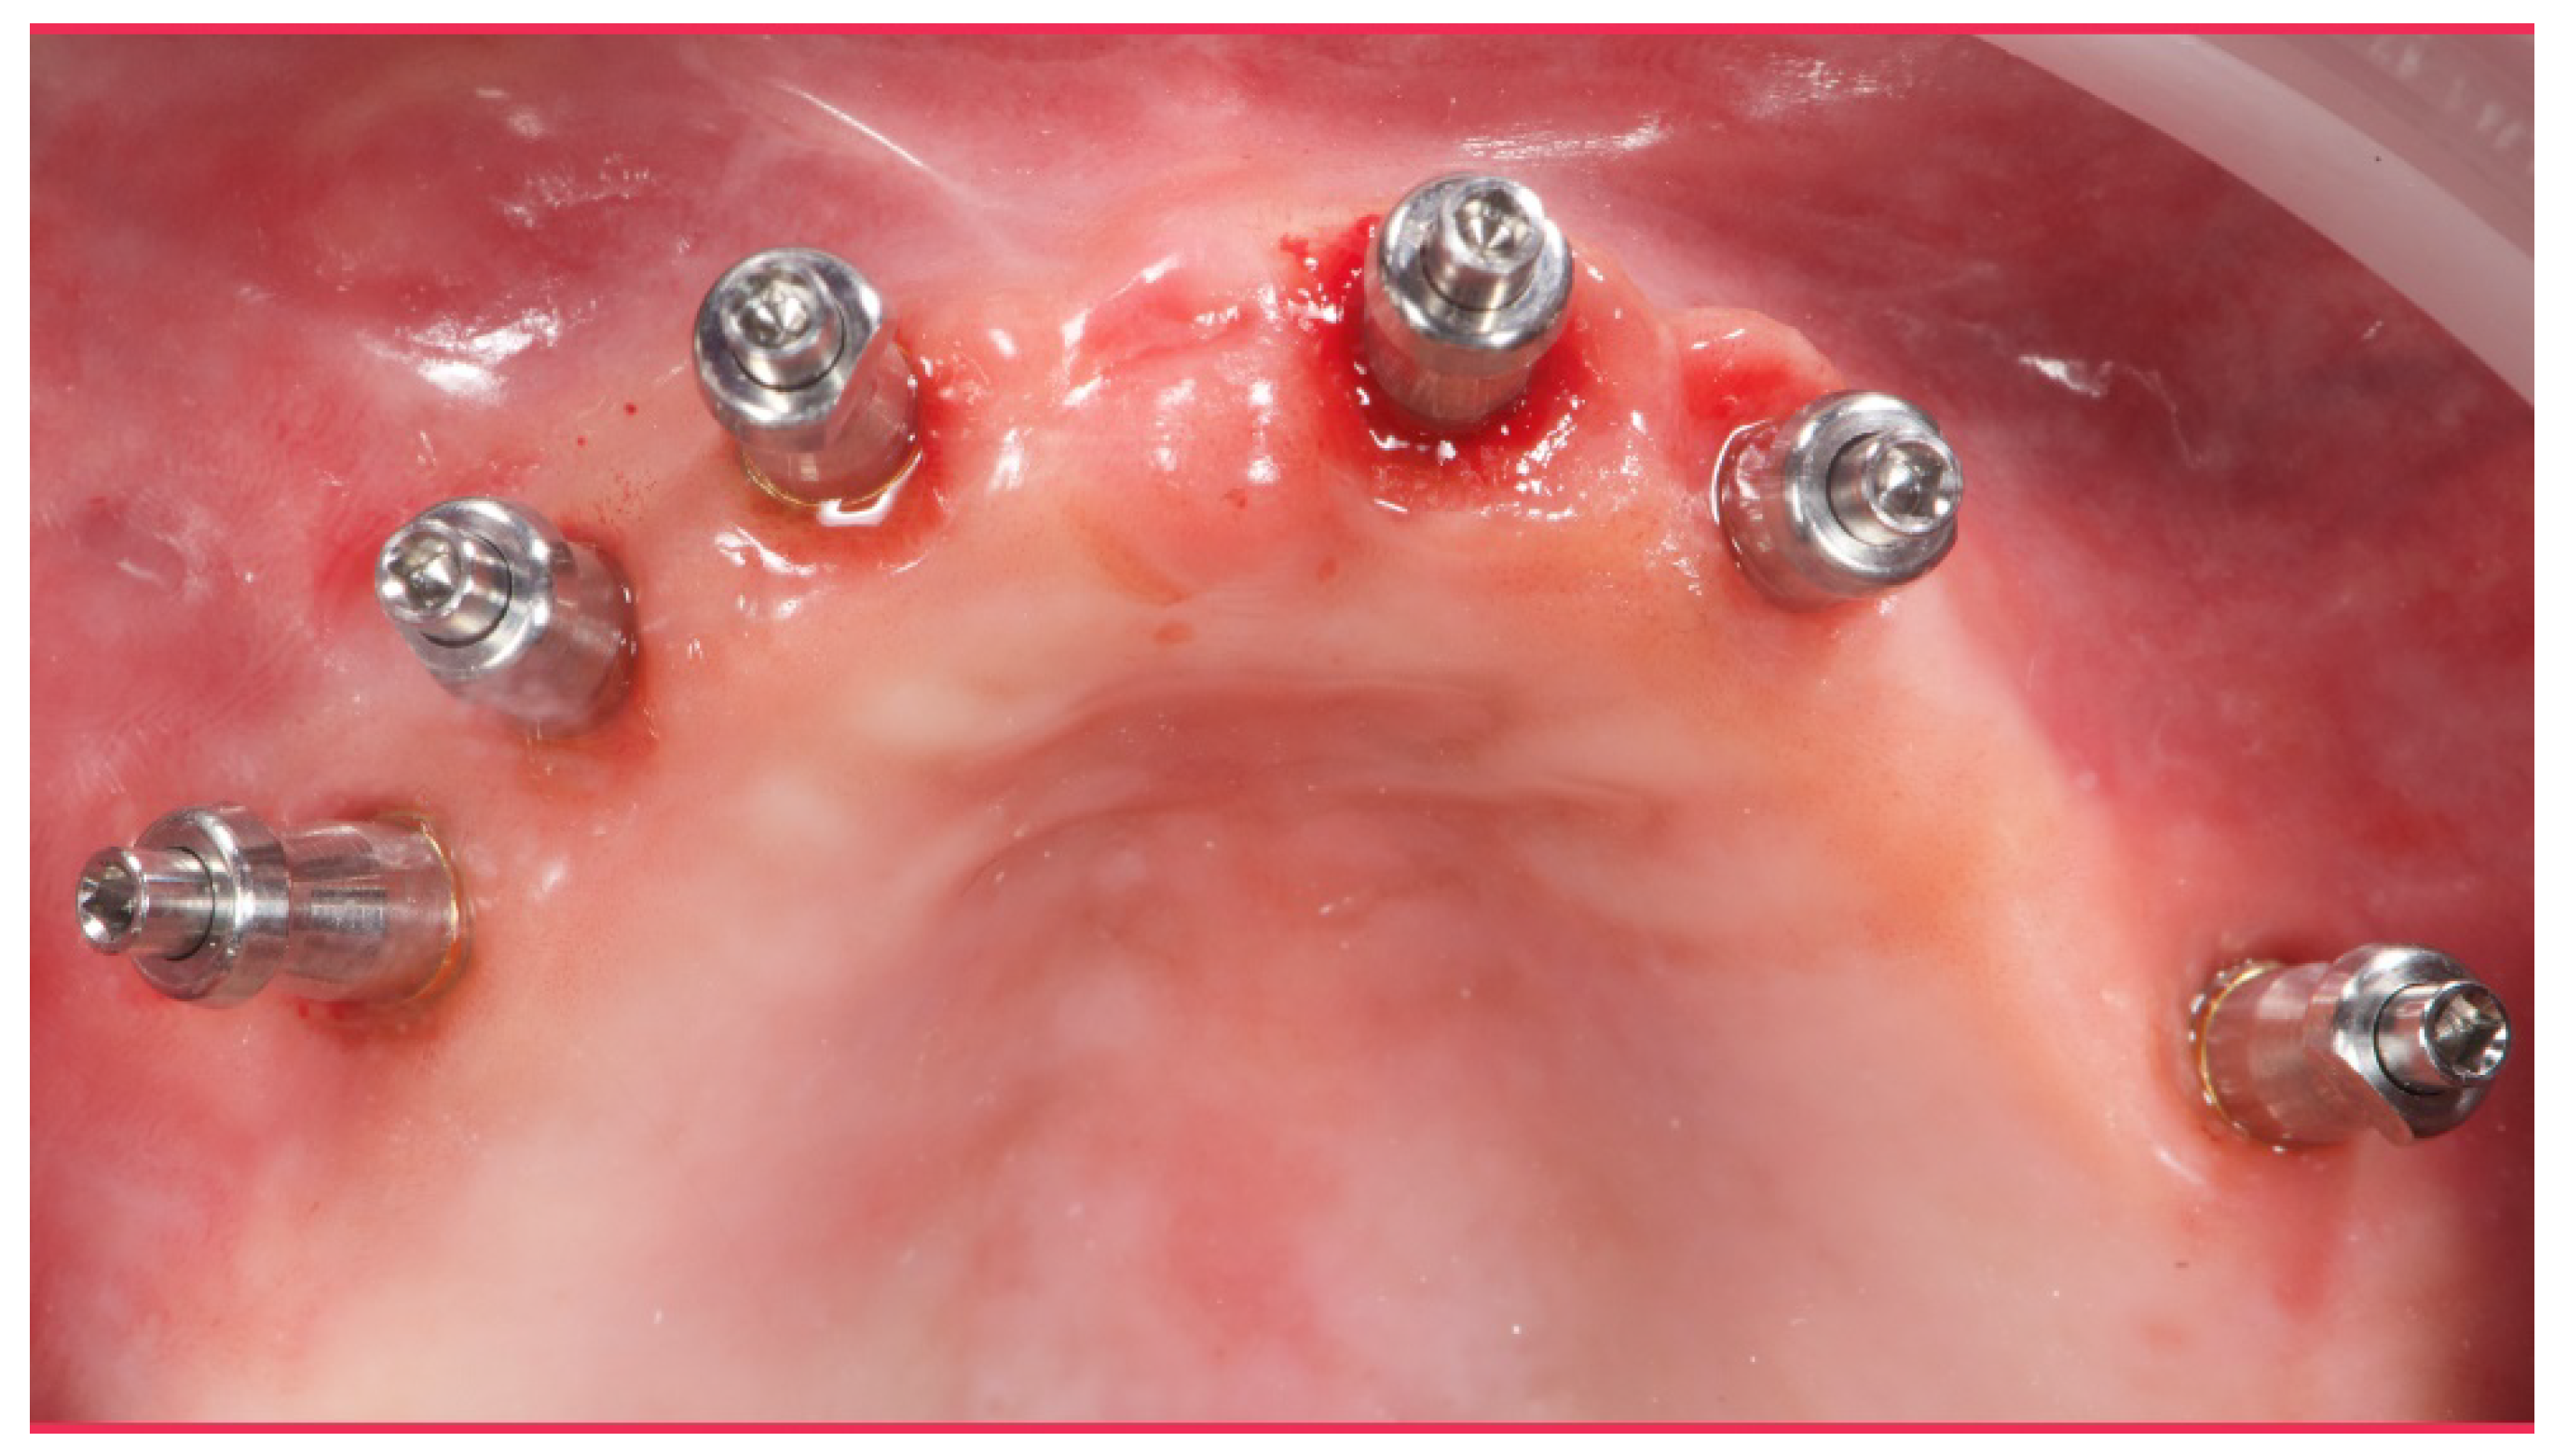

Figure 7.

Scan bodies mounted on OT Equator. Note the strong disparallelism among the dental implants.